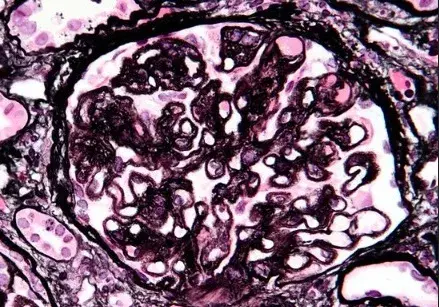

Cefalea, alteración visual y convulsión en un paciente con nefropatía por IgA

Caso clínico publicado en el NEJM: Un hombre de 35 años con nefropatía por IgA acudió a urgencias con síntomas de confusión mental, visión borrosa y convulsiones durante 1 día. Dos semanas antes de la presentación, comenzó a tomar ciclosporina para el tratamiento de la nefropatía por IgA. Su presión arterial era de 160/80 mm Hg. En el examen físico, el paciente estaba somnoliento y presentaba disminución de la agudeza visual. El examen de fondo de ojo fue normal.